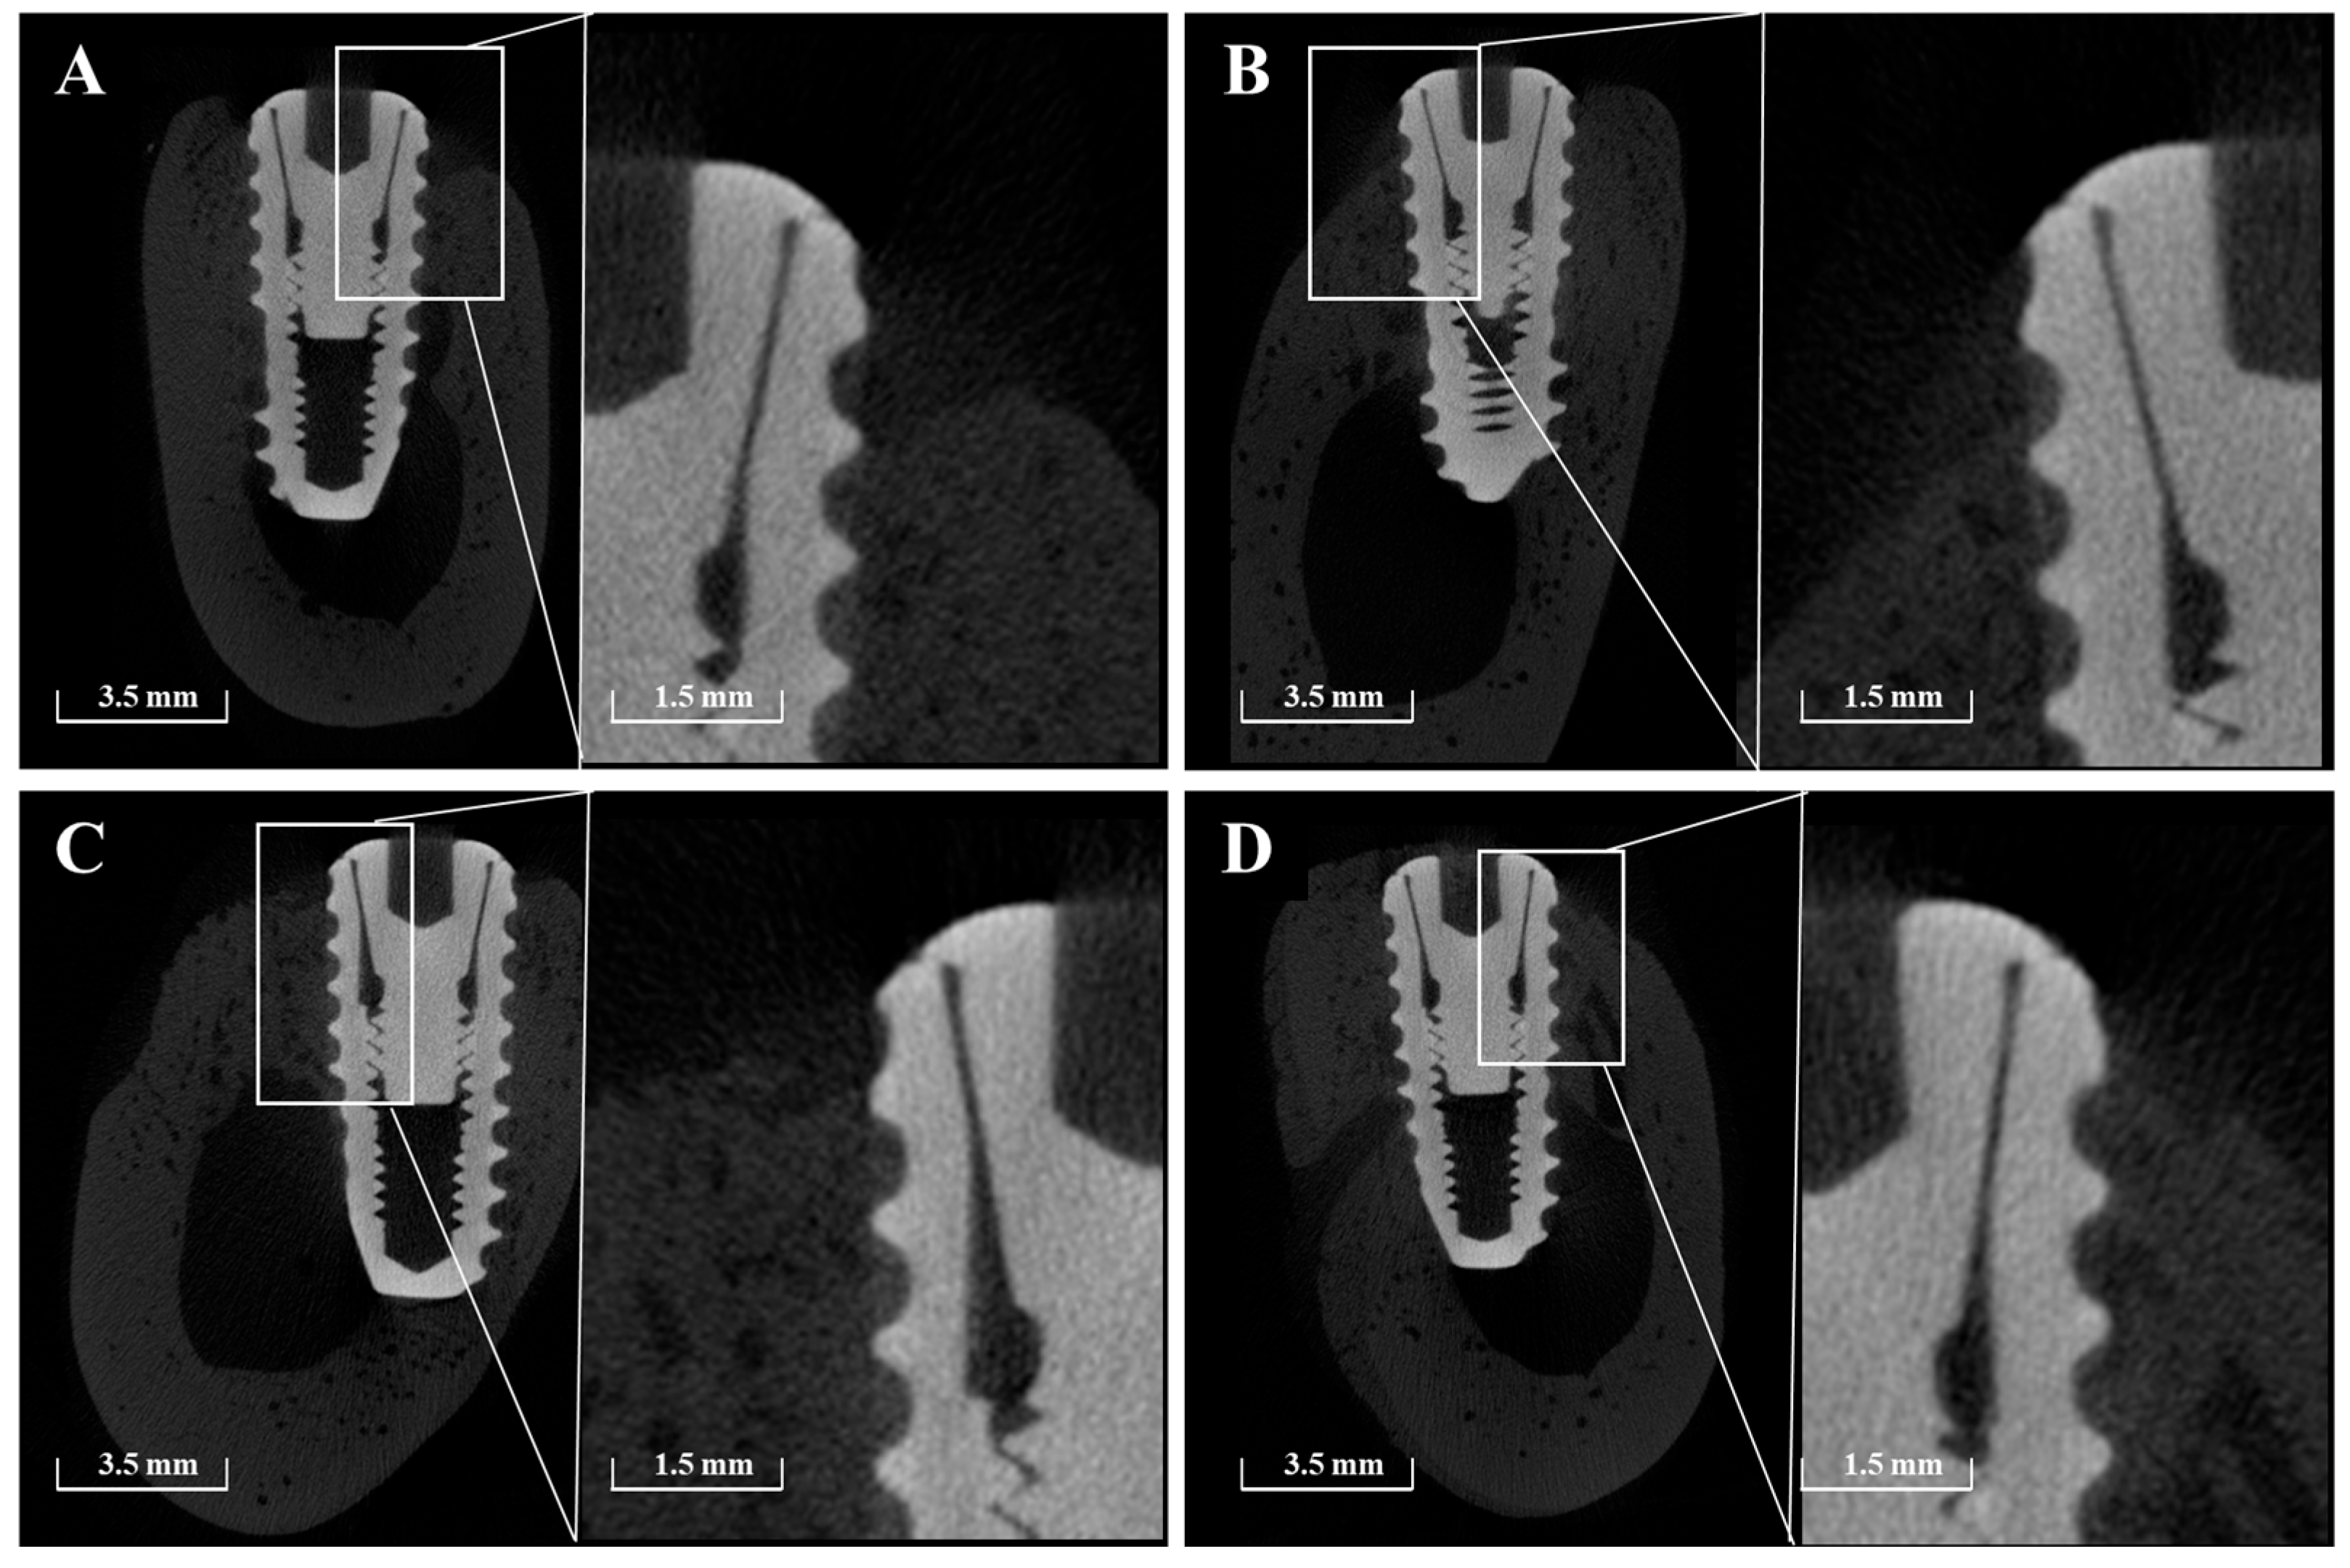

2.2.5. Volumetric Analysis Using Micro-Computed Tomography (μ-CT)

3.2.4. Micro-CT Findings